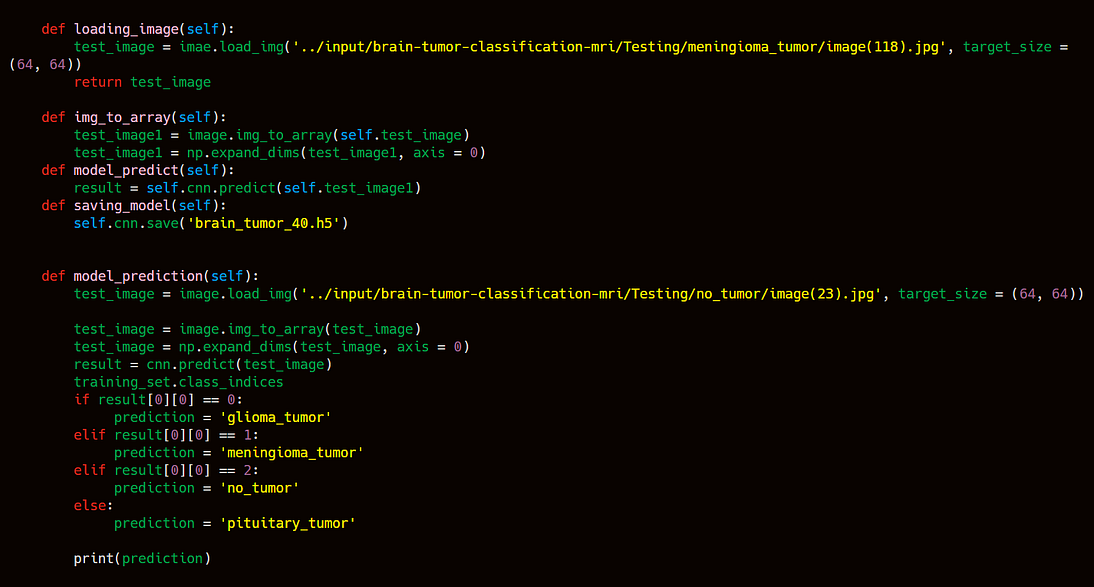

After knowing the classes indices you will find that

index 0 represents → Galioma Tumor

index 1 represents → Meningioma Tumor

index 2 represents → No Tumor

index 3 represents → Pituitary Tumor

After model training we have to save the model in .h5 file. After saving we will put this model into a docker file where we will create a webapp using flask and html, css, javascript. Now the machine learning part is done lets move to DevOps part to do some operation using automation and provisioning tools.